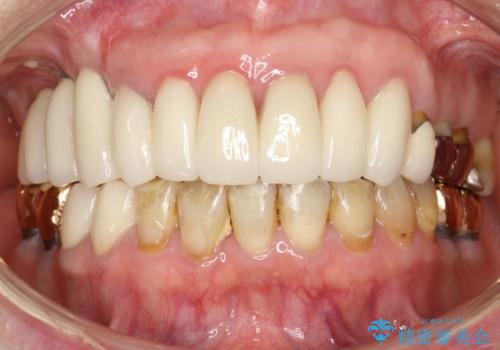

前歯の低クオリティな治療の実態 妥協無い治療で根本からやり治す

- 歯周外科・再根管治療後、クラウンを製作する。

時間をかけ、妥協なく治療を行い、今後の再治療の可能性を極力少なくするために、

費用や時間といった労力がかかってしまうのは当然のことです。

かぶせ物の種類:PFZ standard